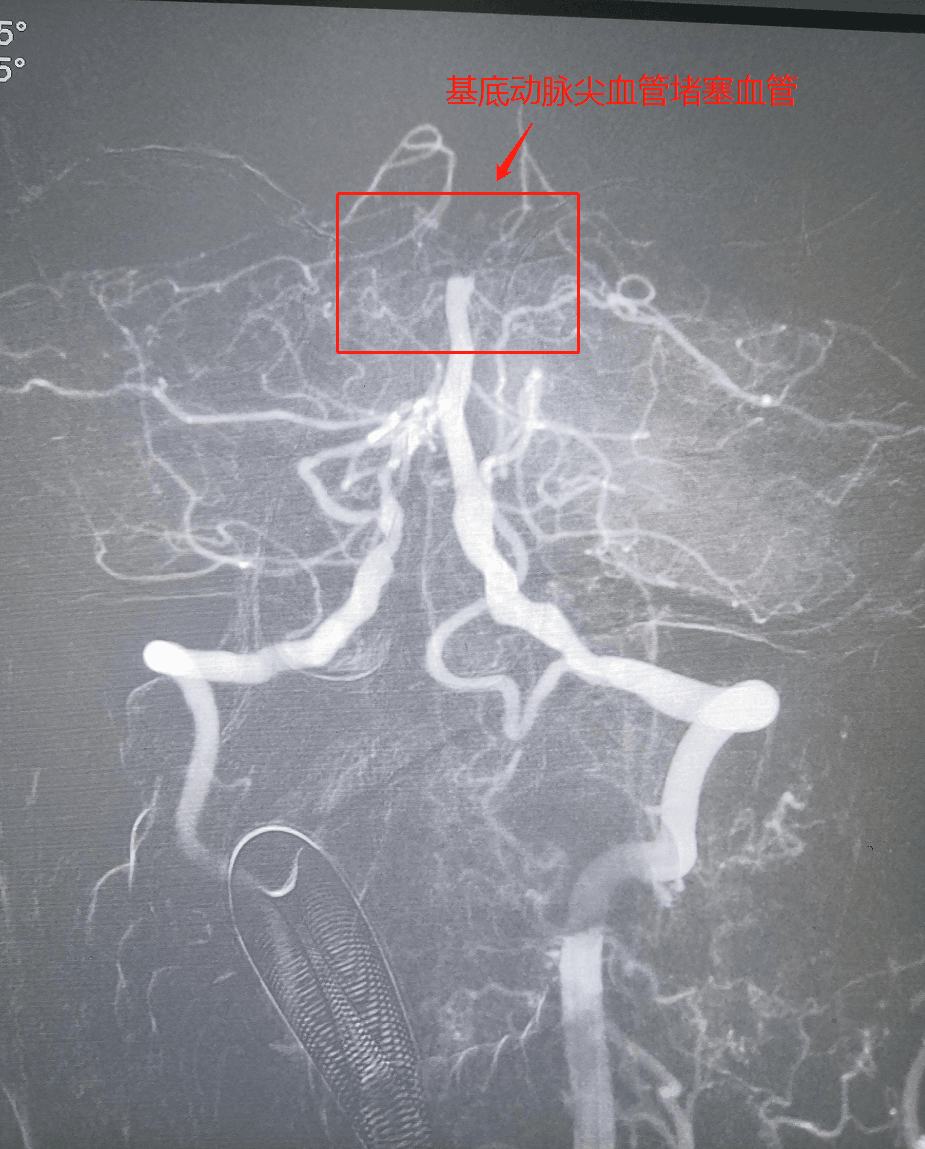

近日,我院接诊一例基底动脉急性闭塞患者。

患者郭大爷,3月16日上午09:00起床服用降压药物时仍感头晕,感左侧面部麻木不适,自觉吐词欠清,再次呕吐非咖啡色样胃内容物2次,家属立即拨打120求助,拨打120过程中,患者出现意识丧失,呼喊、拍打患者不能做出回应,我院急救人员到现场后患者仍呼之不应,立即建立静脉通道、吸氧将患者接回我院,完善头颅CT排除“脑出血”后,遂以“急性脑梗塞”收入我院神经内科。

生命危在旦夕,溶栓刻不容缓!我院的卒中救治团队迅速行动起来,第一时间完成了头部CT、核磁、血管成像评估,化验检查,并迅速在全麻下行静脉溶栓后桥接动脉取栓。